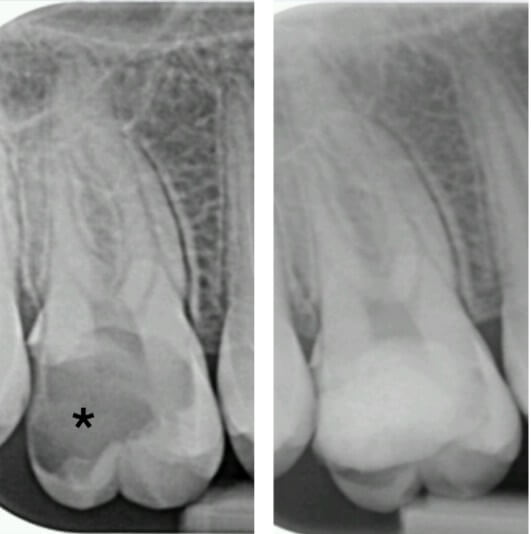

If left untreated, the pulp may become necrotic due to bacterial invasion, potentially resulting in a periapical abscess (Fig. 3). At this point, antibiotic therapy, regularly discussed for misuse in medicine, is often essential alongside surgical interventions such as drainage of the abscess [26]. Once the immediate crisis is addressed, endodontic treatment is necessary to save the affected tooth.

Fig. 3.

Photograph of a gingival fistula (arrow) showing the presence of a periapical abscess abutting the tooth.

The implications of periapical infections are not confined to the mouth; they can act as sources for distant infections, including sinusitis related to dental issues [27] (Fig. 4), infections in prosthetic joints [28], or in rare cases, brain abscesses [29]. According to Deppe et al. [30], oral bacteria may be implicated in approximately 10 to 35% of infective endocarditis cases, highlighting a potential link between oral health and cardiovascular conditions.